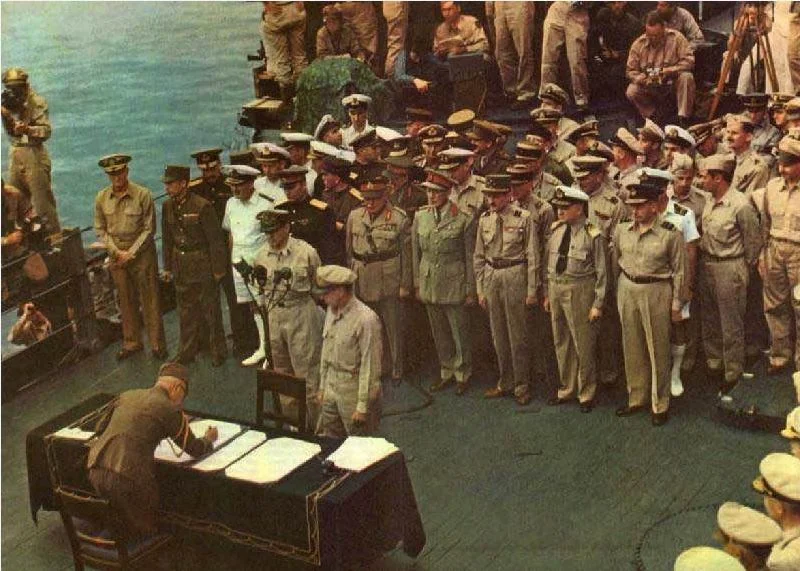

On May 6, 1953, the first successful truly open-heart operation was performed with the use of the heart-lung machine. On that spring day in Philadelphia, John Heysham Gibbon of the Jefferson University Medical Center, using total cardiopulmonary bypass for 26 minutes, closed a large secundum atrial septal defect (ASD) in an 18-year-old woman. Beginning with this case, generations of cardiac surgeons have been able to operate on millions of human hearts.